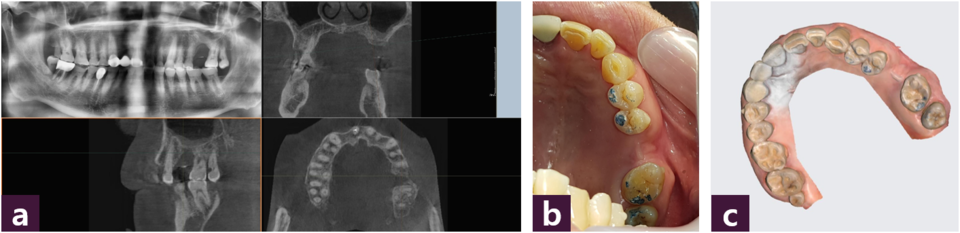

CBCT, intraoral photo, scanner 등 3가지 자료를 준비한다.

먼저 자료들의 정합을 위하여 결손부 치은 및 안정된 유지가 가능한 치아 특정 부위 3군데에 레진을 부착한다. CBCT에서 전치부에서는 sagittal view, 구치부에서는 coronal view를 우선적으로 파악하며, 동시에 apex부분의 axial view에서 골 파괴 양상과 범위를 꼭 확인하여야 한다. Intraoral photo에서는 교합면의 교합점이 반드 시 표현되어야 하며, 폐구시 buccal overjet를 관찰할 수 있어야 한다. IOS scan에서는 왜곡이 없는 범위내에서 최대한 넓게 획득하며, 레 진 랜드마크 등이 잘 표현되어야 한다 [그림 1].

CAD software는 다양한 선택을 할 수 있지만, 본 증례에서는 순수 국내 기술로 원천 기술 및 SW 엔진을 보유하고 있는 3D 산업영상(3dii.net, Seoul, Korea)의 Dentique Guide 및 Dentiq Link를 사용하였다 [그림 2].